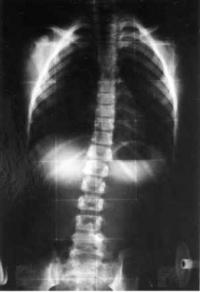

レントゲンやCT検査は、放射線(X線)を使って、体の中の骨を写し出すことができます。

骨にある異変や周辺の変化を画像として見ることができるのです。

たとえば、脊椎(背骨)は、首の部分の頸椎からお尻の突端の仙骨・尾骨まで、

26個の骨が連なっています。

その「骨と骨の間が狭くなっている」「骨の位置がズレている」といった異変は、

画像に映し出すことができます。

レントゲンやCT、MRIの画像を見れば、

「背骨が変形している」 「ズレがある」 「軟骨がつぶれている」

「ヘルニアがある」 「脊柱管(神経管)が狭くなっている」

などということはすぐにわかります。